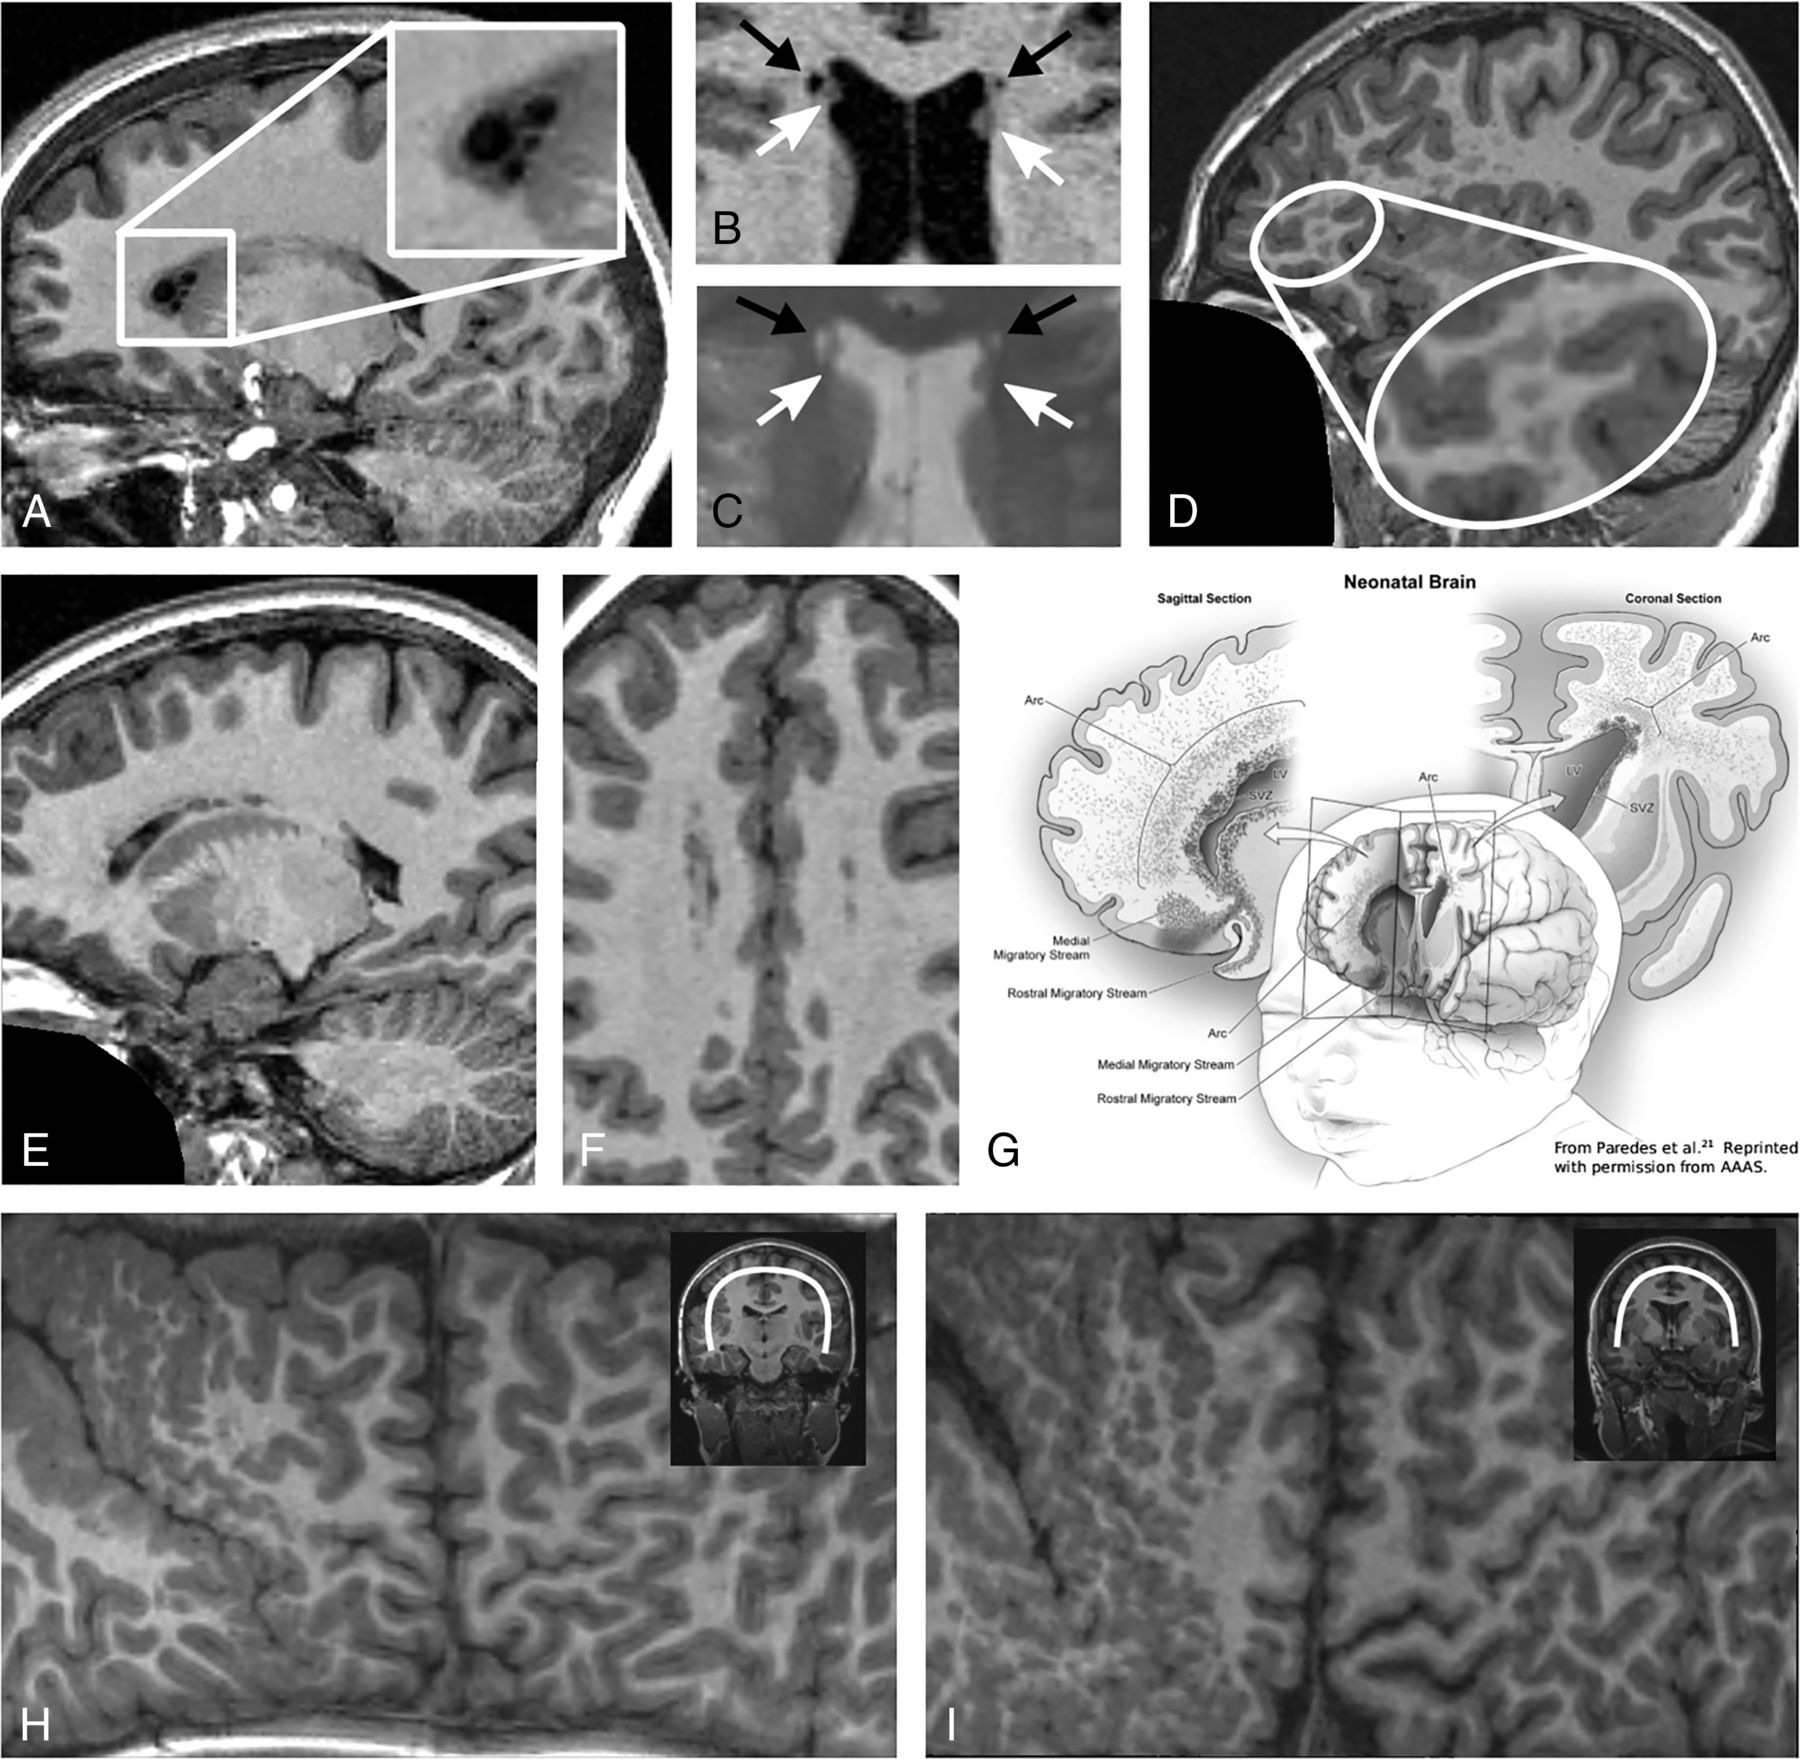

Specifically, in this sample, we found the following morphologic abnormalities: heterotopia (periventricular or in the white matter), periventricular cysts, polymicrogyria, and CSP and/or CV (Fig 1 and Table 2).

Representative examples of morphometric findings in brain MRIs of 6 subjects with 22q11.2DS. Subject 1: Small cysts adjacent to the anterior horns of the lateral ventricles (A). Subject 2: T1WI (B) and T2*WI (C) of bilateral cysts (black arrows, isointense to CSF in both sequences) and periventricular heterotopia (white arrows, cortex-isointense in both sequences). Subject 3: Multiple, perivascular, and frontal heterotopia in the white matter (D). Subject 4: Multiple periventricular heterotopia forming an arcuate structure in the sagittal view with a remarkable overlap with the migratory stream of the Arc cells outlined in G (E, F, and G). The drawing in G is taken from Paredes et al21 (reprinted with permission from American Association for the Advancement of Science), who were the first to identify Arc cells as a population of late-moving neurons at this localization. Subjects 5 and 6: Exemplary Mercator brain projections of 2 of the 3 individuals with polymicrogyria in the peri-Sylvian area of the right hemisphere (H and I).

The heterotopia-like lesions identified on T1WI were also isointense to the cortex on the T2*WI in all individuals with 22q11.2DS and were thus confirmed as heterotopia. The periventricular cystlike lesions identified on T1WI were isointense to the CSF in all except 1 T2*WI (Online Supplemental Data). In 1 subject, a cystlike lesion proved to be a PNH by additional review of the T2*WI. T2*WI was not available for 1 individual with PNH and 1 with a cyst. Heterotopia and cysts occurred mostly in the frontal regions (10/10 PNH, 28/29 heterotopia in the white matter, 9/10 cysts). In 7/29 individuals with 22q11.2DS, the distribution of heterotopia in the white matter exceeded that in the frontal region. heterotopia-like lesions in the white matter were also found in 4 controls on the T1WI. However, these proved to be isointense to the CSF on T2*WI, so they are most likely enlarged perivascular spaces and not heterotopia (Online Supplemental Data).

Heterotopia and cysts frequently appeared together (Online Supplemental Data; not significant after false discovery rate adjustment). Other findings appeared independently. PNH were in all except 2 individuals, multiple (n = 2–13) and bilateral. The cysts were bilateral in 7 individuals, and 6 individuals had multiple cysts (n = 2–12). A single cyst or heterotopion was adjacent to the anterior body of the lateral ventricle. When multiple, they appeared arranged in arching, chainlike structures in the sagittal view (Fig 1). In 19/20 individuals with 22q11.2DS, the CSP occurred in combination with CV; in 1 individual, CSP occurred alone. Polymicrogyria was unilateral, right-sided, and located in the peri-Sylvian area in all 3 individuals (Fig 1).

A DTI study found impaired connectivity, which the authors attributed, among other causes, to ectopic neurons in the white matter.8 In a study investigating epileptic seizures in individuals with 22q11.2DS, 1 subject with unilateral frontal white matter heterotopion was mentioned,18 suggesting that the heterotopia visible on MR imaging may be only the tip of the iceberg. The literature describes an accumulation of nonspecific white matter lesions19,20 in individuals with 22q11.2DS with the same localization and shape as the heterotopia we found in the white matter. The occurrence in the frontal white matter supports the hypothesis of Rezazadeh et al10 that heterotopia in 22q11.2DS might result from arrested Arc migrating cells. Arc cells are a population of late-migrating neurons, identified by Paredes et al.21 These neurons form a caplike structure surrounding the anterior body of the lateral ventricle or an arching structure in sagittal sections in the postnatal infant human brain (Fig 1). They continue to migrate along radial glial fibers tangentially to the walls of the lateral ventricles and along blood vessels into the anterior cingulate gyrus and prefrontal cortex in the early postnatal period, when they differentiate and contribute to inhibitory circuits. Paredes et al21 describe Arc cells as histopathologically organized into 4 tiers from the subventricular zone to the cortex. This distribution of Arc cells led Rezazadeh et al to the hypothesis that the PNH they observed were Arc cells arrested in tiers 1 and 2, and the nodules they observed only microscopically in postmortem examinations were neurons in the Arc tiers 3 and 4. Following this concept, the heterotopia in the white matter that we found on MR imaging might represent larger chains of arrested Arc cells in tiers 3 and 4. In addition to the spatial overlap of Arc cells and heterotopia in individuals with 22q11.2DS, there are also immunohistochemical features supporting the hypothesis of Rezazadeh et al.